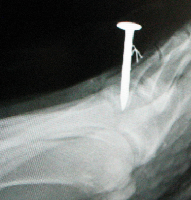

Always take standard radiographs after any puncture wound. X-rays can determine the presence of a retained foreign body or if any osseous structure has been breached. However, X-rays may be inadequate in the detection of small pieces of glass, wood or rubber. In those cases, advanced imaging studies may be necessary.

Computed tomography (CT) can provide superior imaging when it comes to detecting wood deep in tissues.10 Magnetic resonance imaging (MRI) may be helpful, especially in detecting osteomyelitis as MRI provides a precise anatomic location of the infection and assists the surgeon when planning surgical debridement.11 Ultrasound is a very helpful modality in detecting non-radiopaque foreign bodies and is cost-effective.

Pseudomonas is the most common organism responsible for osteomyelitis secondary to puncture wounds.7,16 There is a documented association between rubber soled shoes and Pseudomonal osteomyelitis.16,17 When a nail or other object penetrates the shoe and then the foot, it inoculates the wound with the Pseudomonas organism found on the shoe.